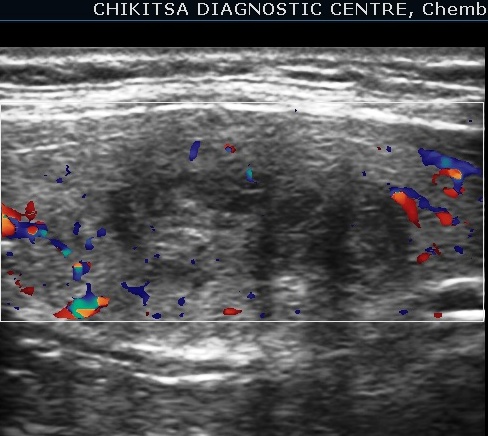

Case 2 : Thyroid Malignancy

A 27 year female complained of swelling in left side neck and it notably increased over a period of 6 months.

Ultrasound Images:

FNAC was done.

Diagnosis on FNAC was " Follicular neoplasm" of the thyroid gland